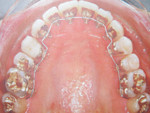

¿Desea conocer mejor nuestra oferta? En nuestra sección de ortodoncia o medicina estetica  obtendrá información detallada.

Puedes ver videos y fotos en instagram: @dr.anasanzcerezo